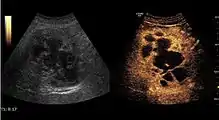

HCC appearance on 2D ultrasound is that of a solid tumor, with imprecise delineation, with heterogeneous structure, uni- or multilocular (encephaloid form). An "infiltrative" type is also described which is difficult to discriminate from liver nodular reconstruction in cirrhosis. Typically HCC invades liver vessels, primarily the portal veins but also the hepatic veins . Doppler examination detects a high speed arterial flow and low impedance index (correlated with described changes in tumor angiogenesis). The spatial distribution of the vessels is irregular, disordered. CEUS examination shows hyperenhancement of the lesion during the arterial phase. During the portal venous phase there is a specific "wash out" of ultrasound contrast agent (UCA) and the tumor appears hypoechoic during the late phase. Poorly differentiated tumors may have a stronger wash out leading to an isoechoic appearance to the liver parenchyma during portal venous phase. This appearance was found in approx. 30% of cases. The described changes have diagnostic value in liver nodules larger than 2 cm.